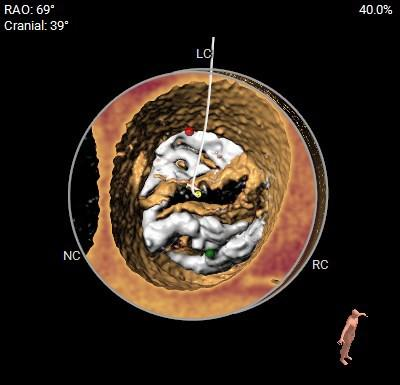

钙化分布

◇ TYPE-0型二叶式主动脉瓣,左右冠不同窦,中重度钙化,钙化主要分布在瓣叶及交界区,左室流出道呈敞口状,综合多平面分析,预估瓣膜释放后有向下位移及瓣周漏可能;